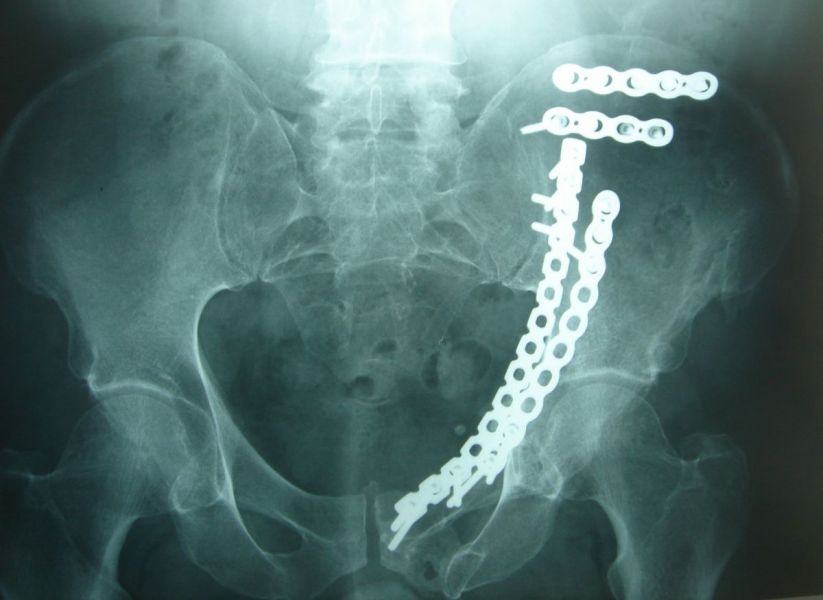

3. Pelvic fracture called also open book fracture in a 27-year-old male.

Treatment: Open reduction internal fixation of pubic symphysis and percutaneous fixation of the left sacroiliac joint

I. Before surgery II. Post-surgery, anteroposterior x-ray of pelvis showing one plate and six screws in pubic symphysis and one large screw in the left sacroiliac joint